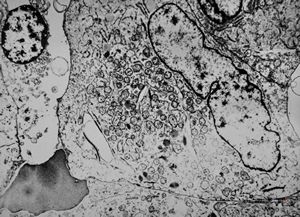

F,39y. | metastatic alveolar sarcoma of soft parts

F,44y. | alveolar sarcoma of soft parts